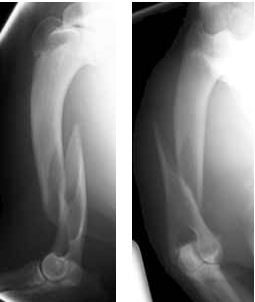

The type of fracture AND the bone that is fractured

Spiral and Humerus

1)Complete/Incomplete? 2)Displaced/Nondisplaced?

3)Open/Closed? 4)What type of Fracture?

5)What Bone?

1)Complete

2)Displaced

3)Closed

4)Avulsion

5)Humerus